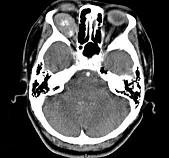

问题 41岁女性,右眼胀痛、眼球外突3月余,体检,发现低头时右侧眼球外突加重,CT检查如图所示,请选择最可能诊断()

选项 A.右侧眶内血管瘤 B.右侧眶内炎性假瘤 C.眼型格氏病 D.右侧眶内神经鞘瘤 E.右侧眶内皮样囊肿

答案 A